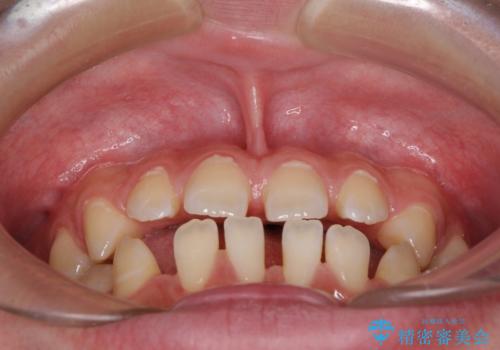

- 上下前歯の隙間を気にして来院された患者様です。

飲み込みや話をするときに舌を突出させる癖が強くあり、それが原因でスペースが空いていました。

舌癖を改善するためのトレーニングを行いながら、ワイヤー装置を用いて前歯の隙間を閉じていくこととしました。